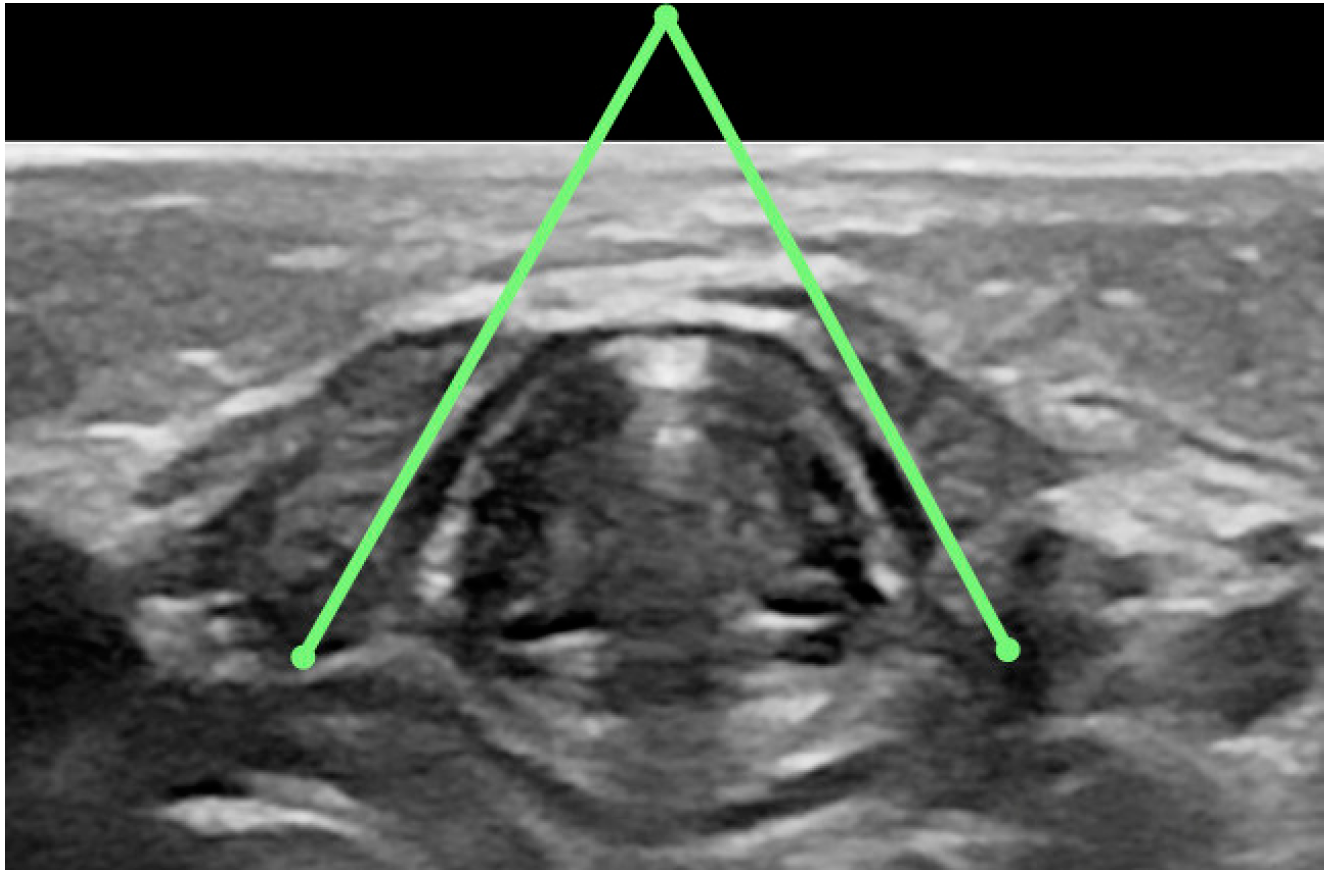

- Surface area of the glottis during calm exhalation (in order to avoid distorting the result of measuring the glottal area using the outline of its visible borders, this measurement will be taken by calculating the area of a triangle, the basis of which will be the width of the glottis, and the height will be the depth of the glottis measured from the posterior part of the anterior commissure to the line drawn to measure glottis width, measurement taken in the transverse plane) (Figure A7);